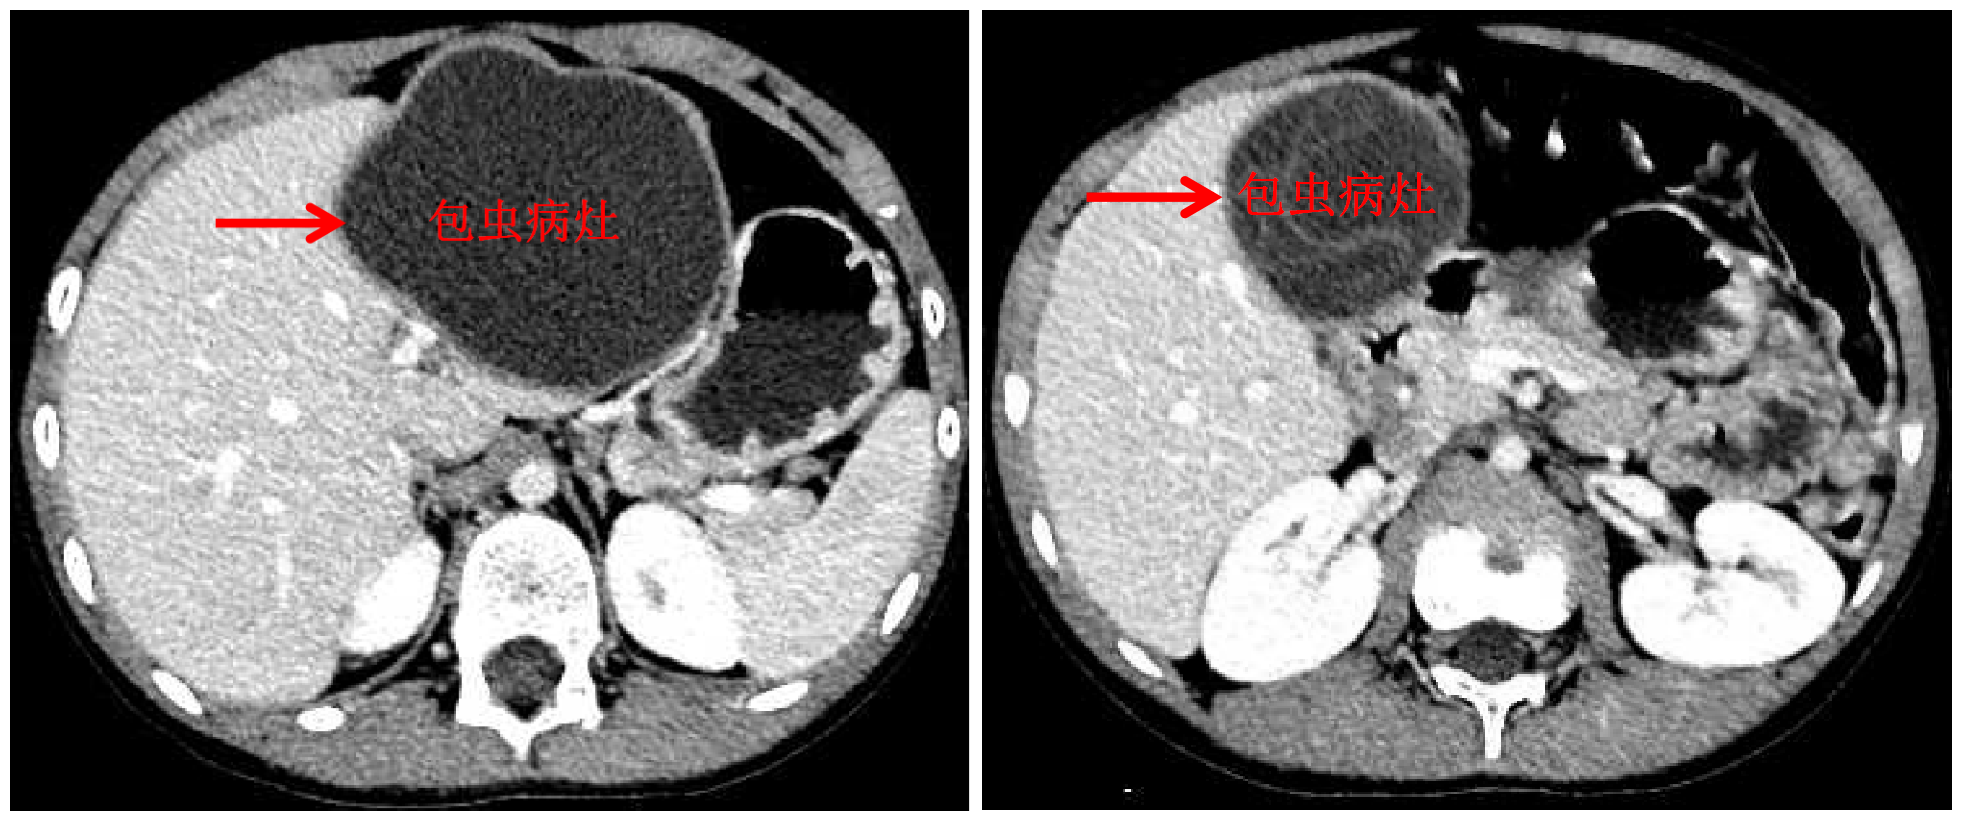

乐鱼(中国)网10月13日电 国庆前,8岁的小扎西被父亲带到了西藏大学附属拉萨市人民医院普外科,此次距离孩子确诊肝包虫病已有一年之久。腹部影像显示,小扎西体内的囊型肝包虫病已经侵袭了左肝大部。

包虫病灶

经三维定量化手术评估及虚拟手术,王学栋认为,肝脏两处病灶虽然巨大,但都位于左半肝,可以挑战腹腔镜解剖性左半肝切除术。9月23日,王学栋联手拉萨市人民医院普外科平措主任等一同为小扎西实施了手术,同术前预测,由于包虫巨大导致术中肝门解剖极为困难,王学栋果断改为前入路左半肝切除术,并同时保留了肝中静脉。在该院强丹主任带领的麻醉科团队和手术室团队的保障下,手术顺利完成,出血量仅100ml。